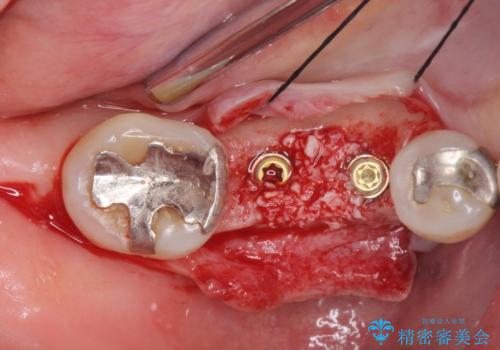

欠損部に1本だけインプラントを埋入しても大きな被せ物になってしまい清掃性が悪くなるので清掃性が良くなるように2本小臼歯用のインプラントを埋入しました。

- 抜歯、歯槽堤保存術・11万円 インプラント体、アバット、仮歯、ジルコニアクラウン・42.9万円×2 骨造成・5.5万円 e-maxインレー・7.7万円 費用は治療当時の料金となります